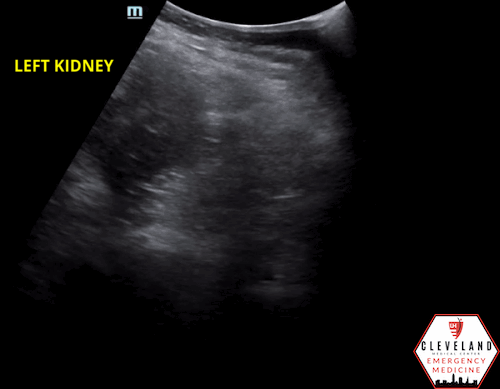

Renal POCUS was performed to evaluate for hydronephrosis and showed the following:

POCUS findings:

There is hydronephrosis of the left kidney. The right kidney is normal-appearing. Bladder views incidentally revealed a large complex, fluid-containing lesion in the pelvis (color doppler negative).